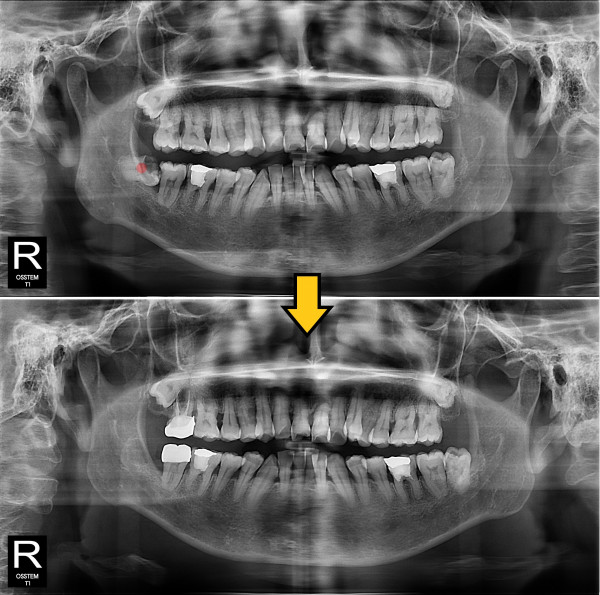

사랑니발치 충치가 심한 사랑니

826e40416d712e6cd444a78bde93df4b_1767857930_3003.jpg